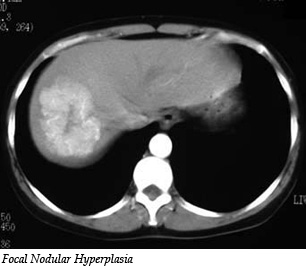

C